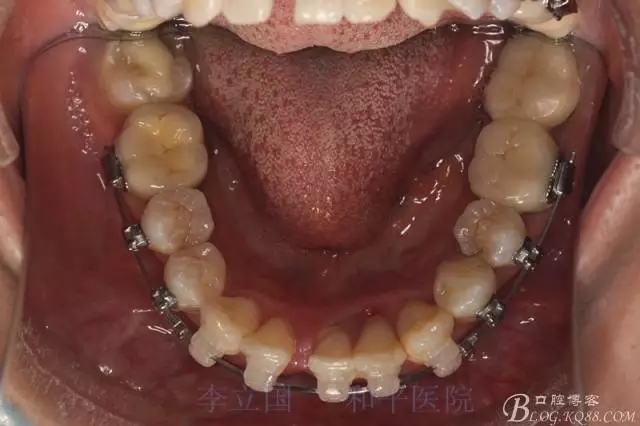

1.拔除14、24、31。

2.Damonclear排齊整平。

3.微種植支抗內(nèi)收上下前牙。

2.磨牙關(guān)系一側(cè)完全遠(yuǎn)中,一側(cè)遠(yuǎn)中尖対尖,采用兩個(gè)上4,一個(gè)下1的拔牙模式。

5.回收過程中,上下前牙輕搖椅,防止覆合加深。